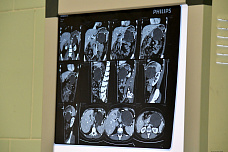

Рак поджелудочной железы встречается не так часто. И о том, что он у больного есть, в большинстве случаев узнают уже слишком поздно, когда операцию делать бессмысленно. Все дело в том, что опухоль поджелудочной железы трудно определить: нужна компьютерная томография с контрастированием или еще более сложные методы диагностики. Поджелудочная железа — один из самых сложных для хирургического вмешательства органов. До недавнего времени её частичная резекция могла быть выполнена только классическим методом «большой» открытой операции, что означало долгий восстановительный период.